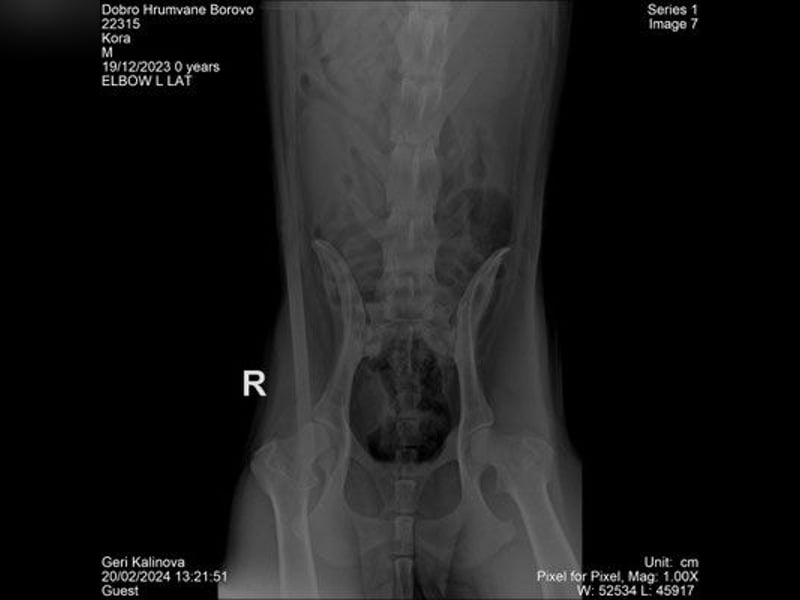

Kurz bevor sie in ihr endgültiges Zuhause ziehen sollte, bekam Cora plötzlich starke Schmerzen und begann zu lahmen. Nach anfänglicher Entwarnung zeigte sich später eine schwere Hüftdysplasie rechts, eine beginnende links sowie ein vermutetes Problem im Lumbosakralbereich, das nur per CT abgeklärt werden kann.